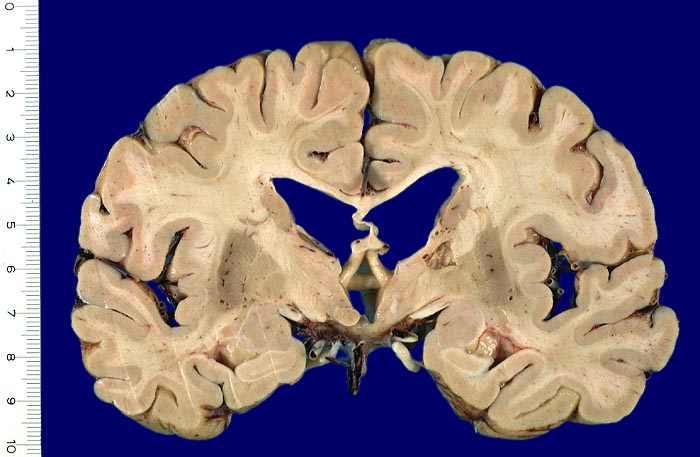

AP/ Anämischer Hirninfarkt

Anämischer Hirninfarkt

Morphologie:

Die morphologischen Veränderungen der Kolliquationsnekrose des Hirngewebes bei anämischer Enzephalomalazie lässt sich in drei Stadien gliedern:

• Frische Nekrose und Demarkation (0-5 Tage): Makroskopisch nach 12 Stunden leichte Erhabenheit erkennbar (Ödem). Erweichung. Unscharfe Mark-Rindengrenze. Mikroskopisch eosinophile Degeneration der Neurone und ödematöser Randsaum.

• Resorption und Abräumung (ab 5. Tag, vorliegender Fall): Mit zunehmendem Alter des Infarktes wird das Gewebe weicher und zerfällt innerhalb einiger Wochen zerfliessend kleinzystisch (Kolliquationsnekrose). Mikroskopisch ab dem zweiten Tag Auftreten von Makrophagen im Randbereich. Durch Phagozytose von Myelinbruchstücken lipidhaltige Vakuolen im Zytoplasma der Makrophagen (=Fettkörnchenzellen). Nervenzellen im Randbereich der Nekrose können das Bild einer ischämischen Schädigung zeigen (Hypereosinophilie). Gefässproliferation. Perifokale Gliose.

• Organisation und Zystenbildung (ab 1-8 Wochen): Übergänge zum Stadium 2 sind fliessend. Vermehrung von Fettkörnchenzellen rund um proliferierte Kapillaren. Endstadium des anämischen Infarktes bildet ein zystischer Parenchymdefekt, im Gegensatz zu anderen Organen (Herz, Niere) findet kein narbiger Umbau statt. Die in der deutschsprachigen Literatur oft erwähnte "Hirnnarbe" bezieht sich auf die reaktive Gliose im Randbereich des Infarktes. Eine reaktive Gliose ist unspezifisch und findet sich in der Nachbarschaft verschiedener Läsionen (beispielsweise Blutungen, Tumoren, Abszesse etc.). Alte abgebaute Infarkte sollen makroskopisch von alten Kontusionsherden abgegrenzt werden. Diese befinden sich praktisch ausschliesslich in frontobasaler oder temporobasaler Lokalisation (> 1436), wo umschriebene Hirninfarkte nicht vorkommen.

Makroskopie

Befund

Pathologischer Befund

Normalbefund